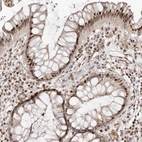

Immunohistochemical staining of human lung shows strong cytoplasmic-nucleus positivity in macrophages.